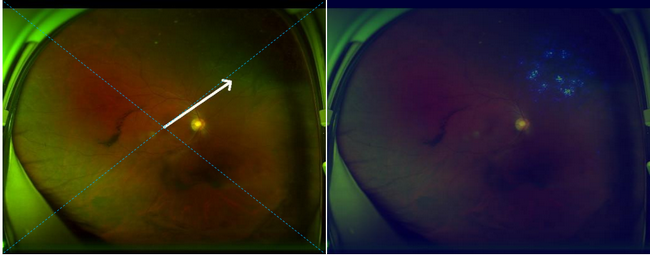

³¬¹ãÓòÑ۵ײÊÕÕÈ˹¤ÖÇÄÜÑÛ²¡É¸²éϵͳ£º£º£ºÍ¼ÖÐÓÒ²à¸ßÁÁÇøÓòΪɸѡ³öÀ´µÄ²¡±ä

×ó²àͼƬ¼ýÍ·Ö¸´¦ÎªÊÓÍøÄ¤ÍÑÀ룬£¬ÓÒ²àͼƬ¸ßÁÁÇøÓòÈÈͼÌáÐÑÊÓÍøÄ¤ÍÑÀëµÄ׼ȷλÖÃ

Õâ¿îϵͳ²»µ«ÄܶÔÑÛµ×ͼÏñ¾ÙÐнâ¶Á£¬£¬Í¬Ê±¿ÉÒÔ×Ô¶¯±ê³ö²¡±ä²¿Î»£¬£¬ÓÐÖúÓÚÒ½ÉúÓÐÕë¶ÔÐԵĽâ¶Á±¨¸æ¡£Í¬Ê±ÈôÊÇÊÓÍøÄ¤ÍÑÀë¼ì²éЧ¹û³ÊÑôÐÔ£¬£¬ÏµÍ³»á×Ô¶¯¸øÓèÌåλָµ¼£¬£¬ÒÔÑÓ»ºÊÓÍøÄ¤ÍÑÀëµÄÏ£Íû£¬£¬½µµÍÊÖÊõ²¢·¢Ö¢£¬£¬¸ÄÉÆ»¼ÕßµÄÊÓÁ¦Ô¤ºó¡£